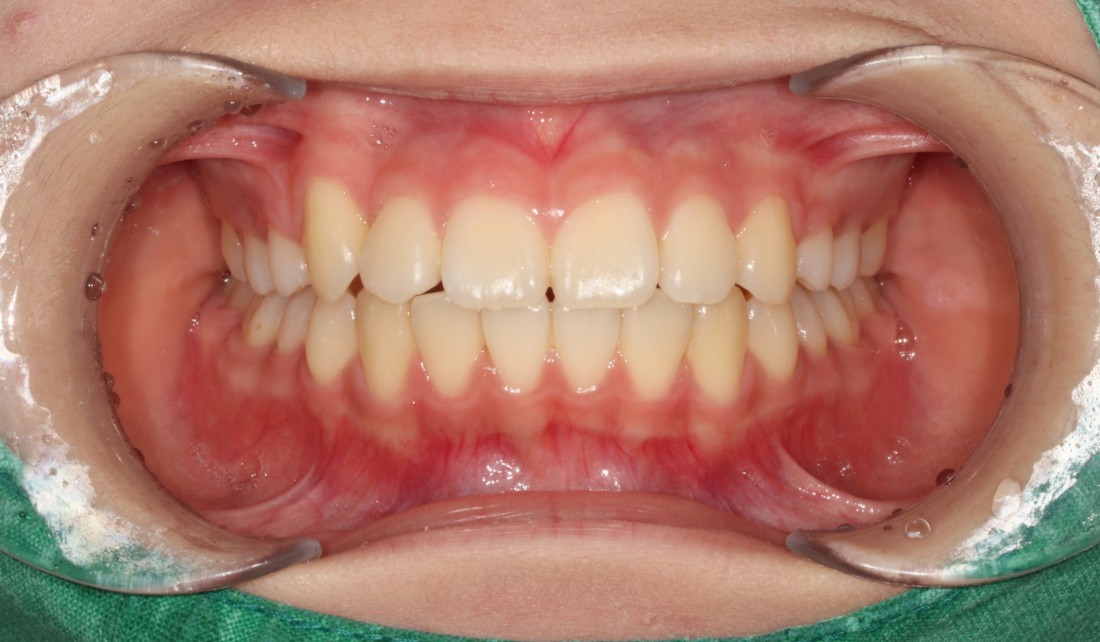

비발치교정만이 무조건 좋은 것이라고

생각하시는 분들이 있을 수 있지만,

발치교정이 필요한 경우에

비발치교정으로 교정하는 경우

치열이 가지런해져도 치아가 돌출되거나

치아 뿌리가 턱뼈 밖으로 밀려나가는 등

다양한 부작용 케이스가 있기 때문에

각 개인별로 최적의 치료계획을 세우는 것이

광주 발치교정 치과의

성공적인 발치교정 노하우입니다.